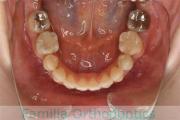

犬歯が八の字になっているので何とかしてほしいということで来院されました。上顎犬歯が左右とも前歯の方に向いていて、一期治療でまずは萌出誘導を行いました。

二期治療は、出っ歯の要素が強かったため、上顎のみ第二小臼歯を抜歯しています。

二期治療は2年強、25回程度の通院が必要でした。犬歯の埋伏歯は、うまく出すことができない場合があったり、出す際に周囲の歯の歯根に傷をつけるリスクがあったりします。